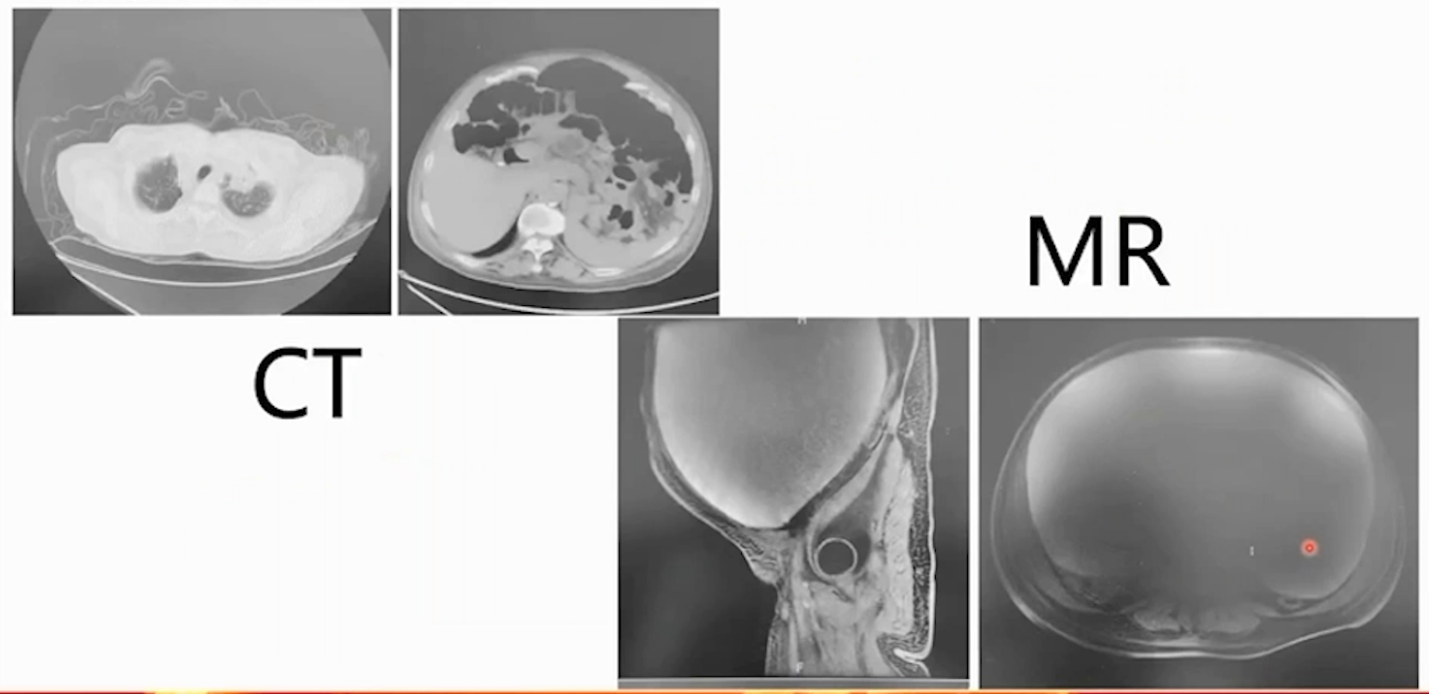

2024-5-10 CT平扫:全子宫+双侧卵巢切除术后,腹盆腔巨大囊性占位,腹盆腔内器官受压移位,腹壁软组织水肿。左肺上叶、右肺下叶占位,较前增大;双肺多发结节,较前明显增多、增大,均考虑转移进展。左侧胸腔积液并左肺下叶膨胀不全,较前新发。左侧第10后肋局部骨质破坏,较前新发,转移可能。

2024-5-26 MR增强:腹盆腔巨大囊性信号灶,最大横截面大小约27.5cm×17.7cm,其内局部多发乳头状突起,最大截面3.3cm×2.8cm,无明显强化,考虑残存附件上皮来源可能。